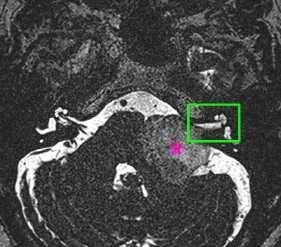

МРТ головного мозга. Шваннома с компонентом внутри канальца.

МРТ головного мозга. Т1-взвешенная корональная МРТ с контрастированием. Полностью внутриканальцевая невринома.

Вестибулокохлеарный нерв (VIII) состоит из 4 пучков. Опухоли происходят обычно из вестибулярной его части. Шваннома - инкапсулированная доброкачественная (градация 1) опухоль, происходящая из дифференцированных неопластических шванновских клеток оболочек периферических нервов. Невриномы ММУ составляют около 3% опухолей головного мозга. Часть шванном (двухсторонние слуховых нервов) связана с НФ 2 типа. Пик частоты между 40 и 60 годами. Растут медленно и крайне редко малигнизируются. Клинические проявления связаны с нарушением функции нерва и компрессией ствола. Шваннома может происходить из любого отрезка по ходу нерва и хорошо прослеживается при МРТ области ММУ. Невринома видна как на Т2-взвешенных, так и на Т1-взвешенных МРТ в виде округлого образования. Невриномы хорошо и равномерно усиливаются после МРТ с введением контрастного вещества. Невриномы области цистерны могут иметь компонент во внутреннем слуховом проходе, особенно, хорошо видимый при МРТ головного мозга с контрастированием. Изредка встречаются невриномы полностью расположенные внутри канальца. Они составляют наибольшую диагностическую сложность при МРТ, требуют тонких срезов и контрастирования. Менингиомы ММУ обычно типично расположены и при МРТ имеют характерную форму и типичные черты при МРТ с контрастированием. Однако редко встречаются внутриканальцевые менингиомы. При МРТ они неотличимы от неврином. Холестеатомы при МРТ имеют смешанную интенсивность сигнала, в зависимости от их содержимого. На диффузионно-взвешенных МРТ холестеатомы обычно яркие.